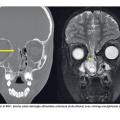

Bien que rare, il faut suspecter une rhinorrhée cérébrospinale devant un écoulement « eau de roche » apparaissant lorsque la tête est penchée en avant. Le dosage de la ß-2-transferrine (positif s’il s’agit de LCR) aide au diagnostic. Une imagerie de la base du crâne (scanner et/ou IRM) est alors réalisée pour déterminer l’origine (fig. 2) : post-traumatique (le plus souvent), post-chirurgicale ou secondaire à une malformation congénitale.

Scanner du massif facial (fig. 3) et bilan général pluridisciplinaire sont essentiels car cette affection s’intègre fréquemment dans un syndrome polymalformatif (rare, appelé CHARGE). Le traitement est chirurgical.